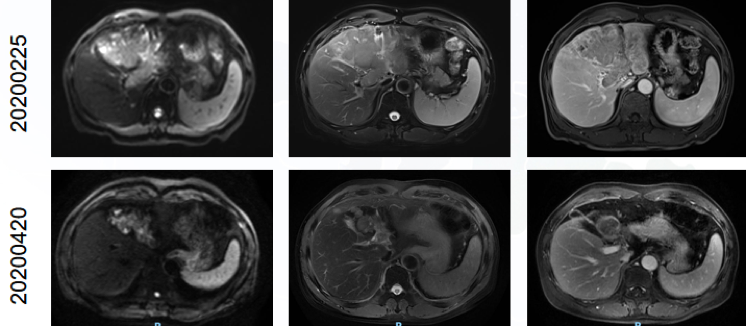

患者男性,64岁;2020年2月主因上腹部不适就诊于外院;2020年2月21日外院腹部彩超示:肝左叶占位性病变,建议进一步检查。2020年2月25日我院MR:肝硬化,肝左叶异常信号肿物影,考虑肝癌,请结合临床;门静脉主干及左侧分支内充盈缺损,考虑癌栓;胰尾部结节影,考虑副脾(图1)。HBV( );否认高血压、冠心病、糖尿病病史。考虑为巴塞罗那分期(BCLC)C期肝癌、中国肝癌分期(CNLC) Ⅲa期肝癌,Child-Pugh分级为A级。

图1.入院MR检查

2020年4月复查MR示:肝左叶病变较前明显缩小,伴强化幅度明显减低,肝左叶萎缩伴信号减低,门静脉主干及右分支管腔内栓子消失,门静脉左支管腔内栓子范围缩小(图2)。

图2.2020年2月和2020年4月MR